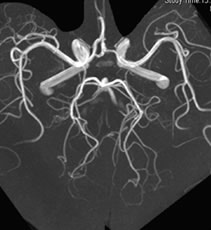

| MRA(エムアールエー) | 脳血管や頚動脈を立体的に描出 |